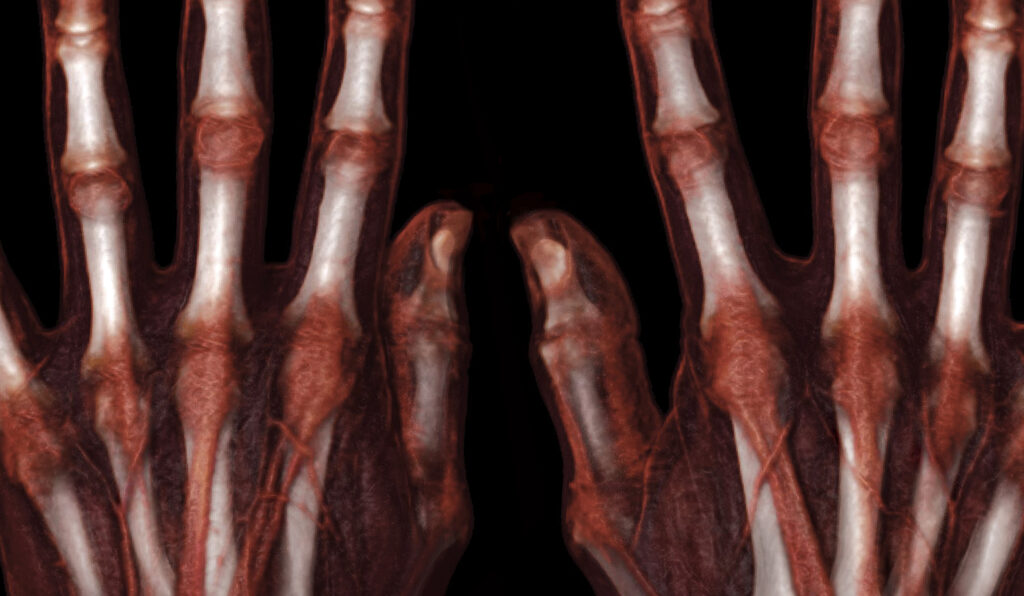

Musculoskeletal

A suite of advanced imaging workflows for CT and MR to facilitate assessment, diagnosis and treatment of musculoskeletal disorders.